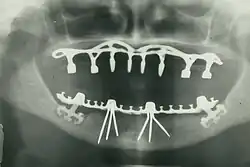

- Oral and maxillofacial radiology – the study and radiologic interpretation of oral and maxillofacial diseases.

The modern movement of evidence-based dentistry calls for the use of high-quality scientific research and evidence to guide decision-making such as in manual tooth conservation, use of fluoride water treatment and fluoride toothpaste, dealing with oral diseases such as tooth decay and periodontitis, as well as systematic diseases such as osteoporosis, diabetes, celiac disease, cancer, and HIV/AIDS which could also affect the oral cavity. Other practices relevant to evidence-based dentistry include radiology of the mouth to inspect teeth deformity or oral malaises, haematology (study of blood) to avoid bleeding complications during dental surgery, cardiology (due to various severe complications arising from dental surgery with patients with heart disease), etc.